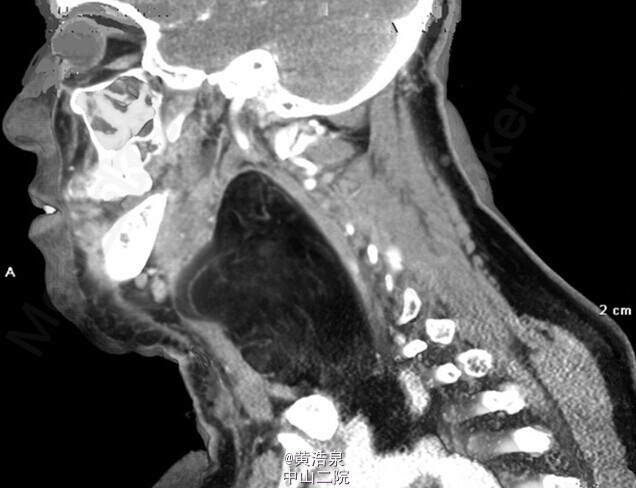

患者女性,53 岁,左侧颈部出现无痛性肿块(缓慢增大),体重无明显减轻,无发热及颈部挫伤史。颈部 CT 增强扫描 .可见一个巨大的、界限清楚的低密度影团块,由咽后部向纵隔扩展。团块内无增强效应,无钙化。HE 染色证实为脂肪瘤。